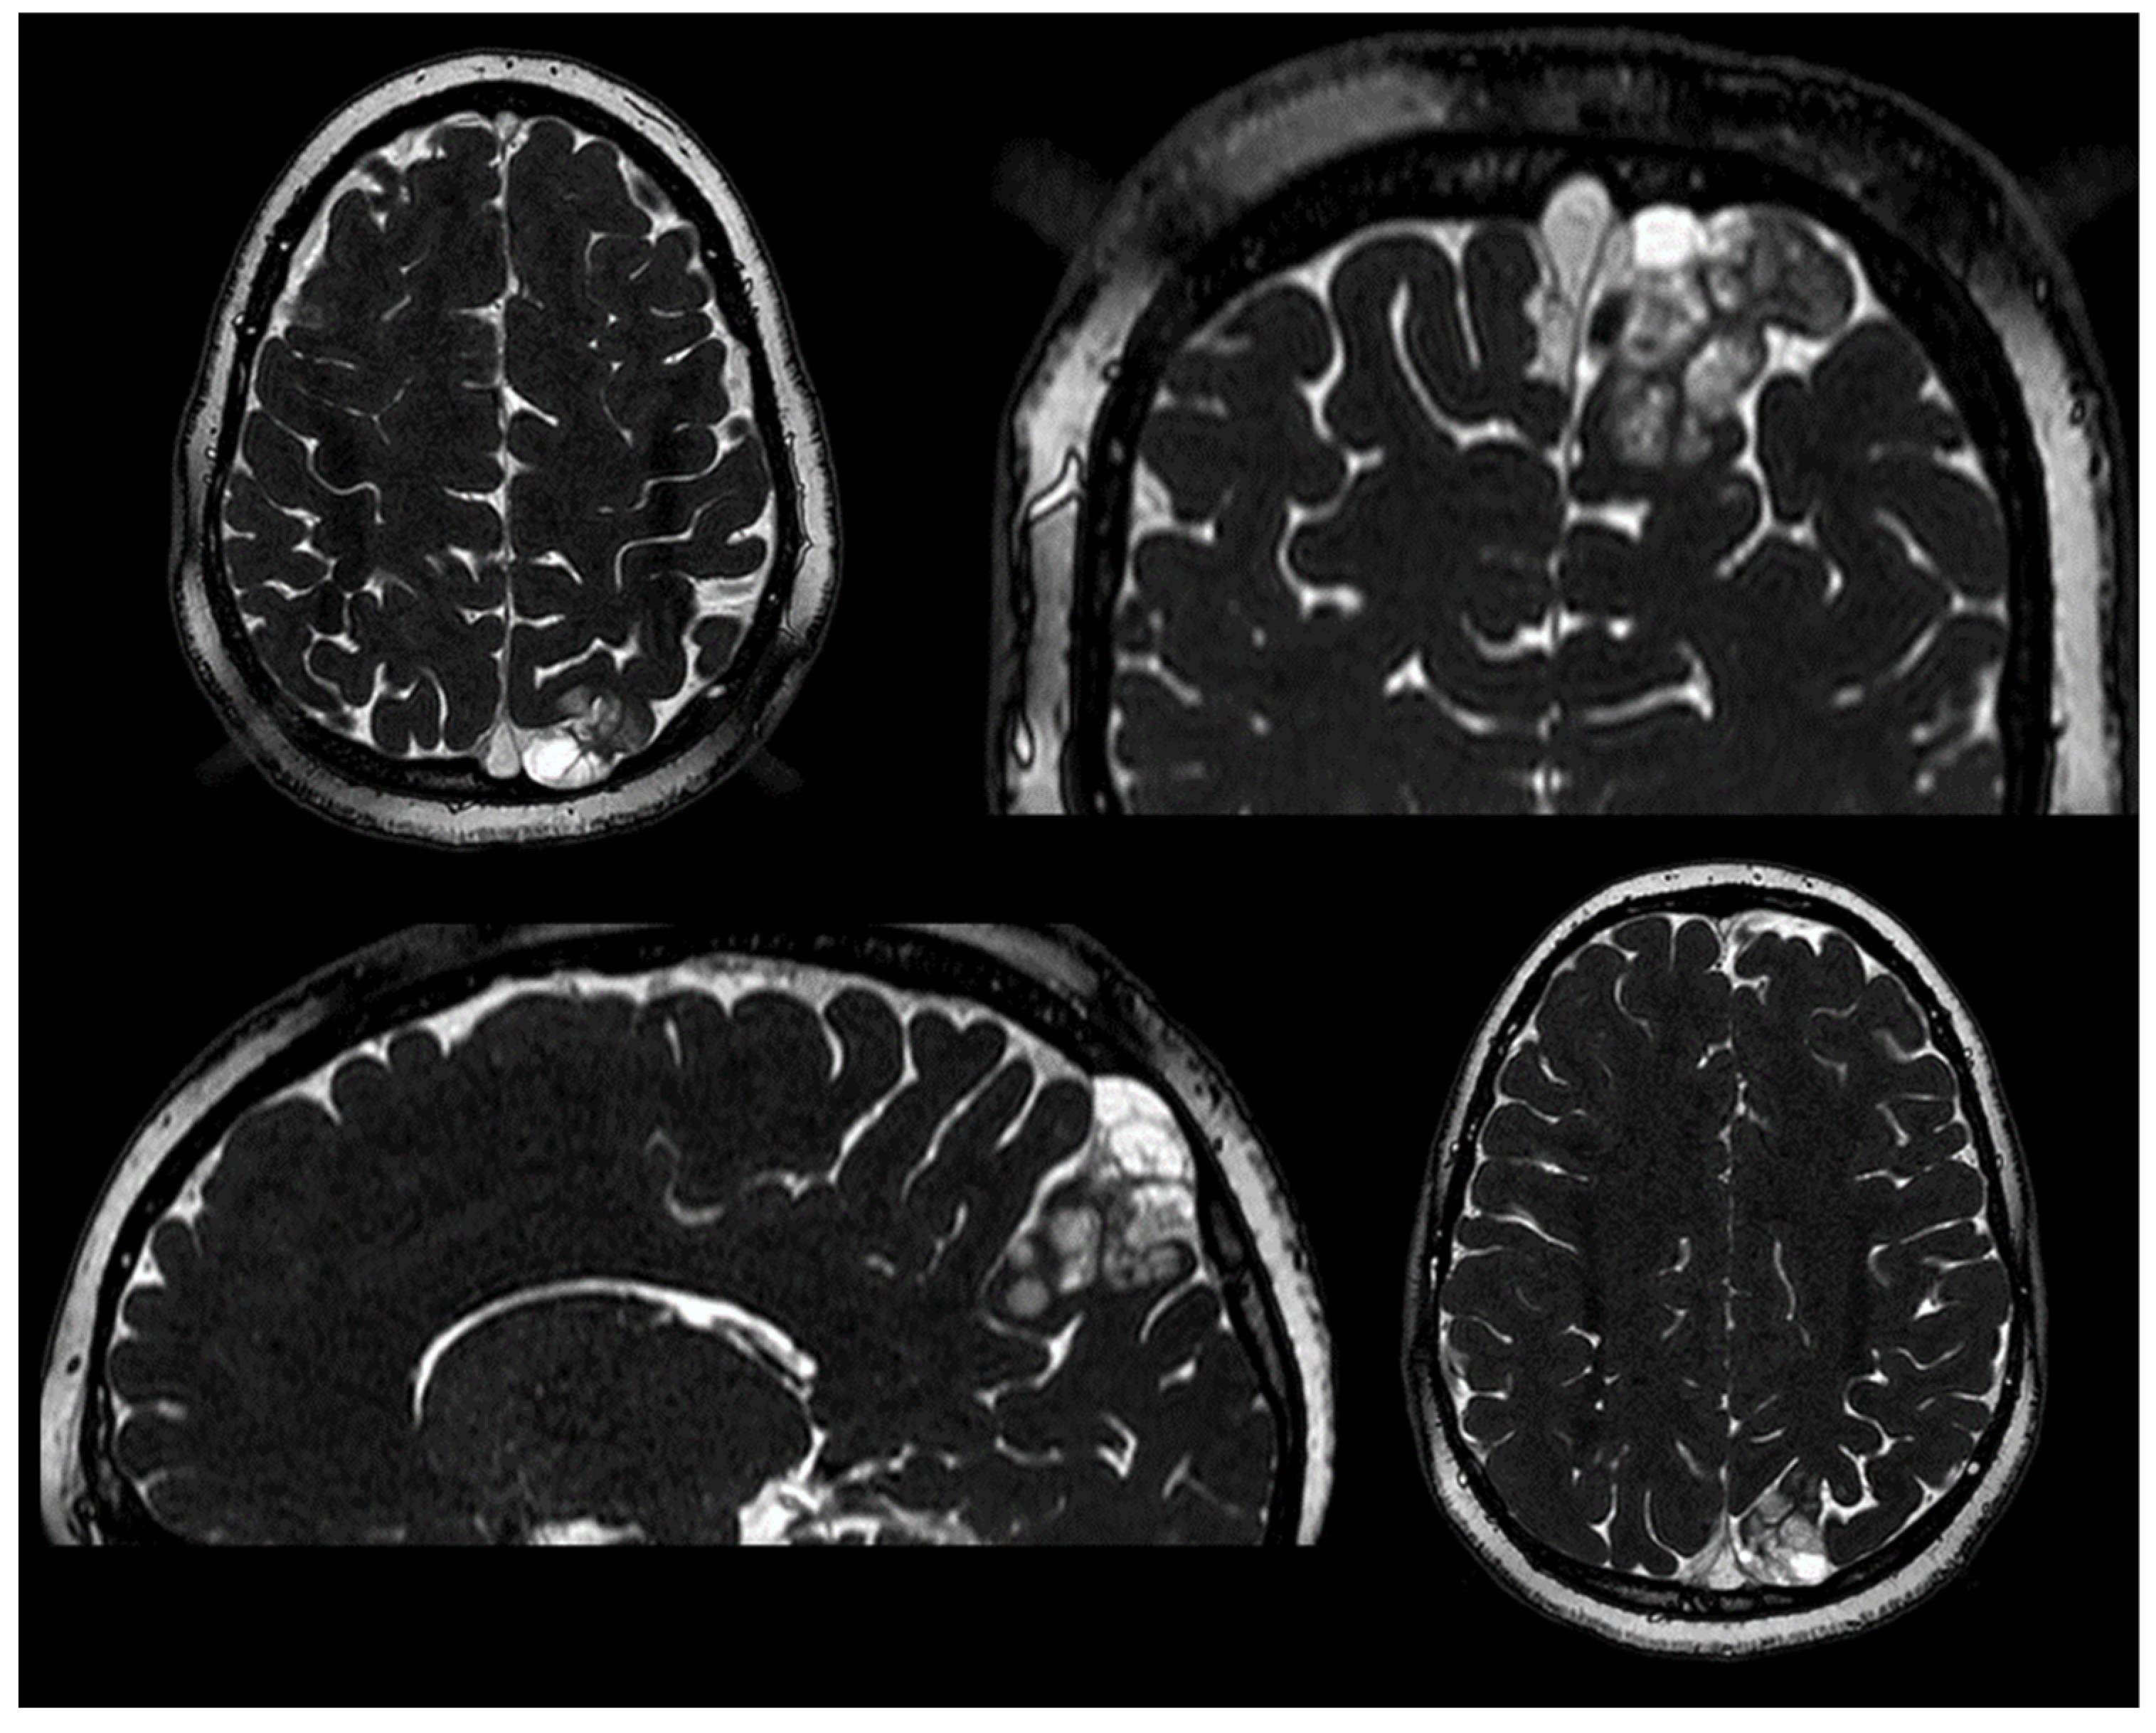

| Our case | 2023 | 8 | M | parietal | L | YES | GTR | NO |